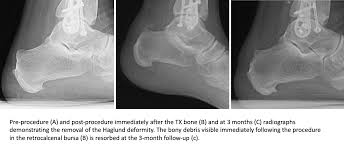

Interesting radiology cases from daily practice and a personal reference. This deformity leads to retrocalcaneal bursitis. It refers to the mechanical irritation between the posterior section of the calcaneus (heel bone) and the achilles tendon. The authors describe a new method of radiologic measurement of haglund's deformity, based on a radiologic study of 31 feet operated for posterior heel pain and more especially for calcaneal tendinopathies related to deformity of the calcaneus, and on a series of 60 asymptomatic feet. Operative management of haglund's deformity in the non athlete:

The authors describe a new method of radiologic measurement of haglund's deformity, based on a radiologic study of 31 feet operated for posterior heel pain and more especially for calcaneal tendinopathies related to deformity of the calcaneus, and on a series of 60 asymptomatic feet. As associated problems such as heel bursitis settle, the size of the lump should reduce, but the bony why is it called haglunds deformity? Radiographic evaluation of haglund's deformity. Haglund deformity is most common in young women who wear high heeled shoes or pumps. This deformity leads to retrocalcaneal bursitis. Haglund's deformity is named after patrick haglund, who defined the condition in 1927. Haglund's deformity can cause the development of bursitis, which is a painful condition in the heel. Haglund's syndrome is a group of signs and symptoms consisting of haglund's deformity (which is an exostosis of the posterior calcaneal tuberosity) in combination with retrocalcaneal bursitis.

Correct shoes that are supportive may prevent it. As associated problems such as heel bursitis settle, the size of the lump should reduce, but the bony why is it called haglunds deformity? Radiographic evaluation of haglund's deformity. The authors describe a new method of radiologic measurement of haglund's deformity, based on a radiologic study of 31 feet operated for posterior heel pain and more especially for calcaneal tendinopathies related to deformity of the calcaneus, and on a series of 60 asymptomatic feet. This deformity leads to retrocalcaneal bursitis. Haglund deformity, also known as a pump bump, bauer bump, or mulholland deformity, is defined as bony enlargement formed at the posterosuperior aspect of the calcaneum. Haglund's deformity is a bony enlargement at the level of the posterior part of the heel. The primary symptom of haglund's deformity is pain at the back of the heel. Haglund's deformity is named after patrick haglund, who defined the condition in 1927. There is a noticeable swelling on the back of heel also called bump. This includes home remedies and. Haglund's deformity is a bony enlargement on the back of the heel. Haglund's syndrome is a group of signs and symptoms consisting of haglund's deformity (which is an exostosis of the posterior calcaneal tuberosity) in combination with retrocalcaneal bursitis.

Radiographic evaluation of haglund's deformity.

Haglund deformity, also known as a pump bump , bauer bump, or mulholland deformity, is defined as bony enlargement formed at the posterosuperior aspect of the calcaneum. You may see reddening and swellings at the heel, which may be very. However, often patients will present with a combination of achilles tendinopathy, retrocalcaneal bursitis or retrocalcaneal exostosis in addition to a haglund's deformity. The authors describe a new method of radiologic measurement of haglund's deformity, based on a radiologic study of 31 feet operated for posterior heel pain and more especially for calcaneal tendinopathies related to deformity of the calcaneus, and on a series of 60 asymptomatic feet. Haglund deformity, also known as a pump bump, bauer bump, or mulholland deformity, is defined as bony enlargement formed at the posterosuperior aspect of the calcaneum. Haglund's deformity also goes by the name of haglund's disease and pump bump. It affects the bone and the soft tissues. Haglund's deformity is an abnormal bump in the heel bone. Halgund's deformity is a condition in which a bony enlargement is formed in the heel. Operative management of haglund's deformity in the non athlete: Haglund's deformity is a bony enlargement at the level of the posterior part of the heel. Correct shoes that are supportive may prevent it. An example is haglund's deformity, a condition caused by a bump on the back of the heel.

Radiographic evaluation of haglund's deformity. The soft tissue near the achilles tendon becomes irritated when the bony enlargement rubs against shoes. Pump bump is named after patrick haglund, a swedish orthopedic surgeon, who first described the condition back in 1927. 1 an isolated haglund's deformity can lead to posterior heel pain in runners due to adjacent soft tissue impingement by the heel counter. Related online courses on physioplus. When this bony enlargement rubs against the achilles tendon and overlying bursa, inflammation of the retrocalcaneal bursa occurs. Haglund's deformity is where bone grows on the heel bone (calcaneus). Haglund's deformity is named after patrick haglund, who defined the condition in 1927. Haglund's deformity can cause the development of bursitis, which is a painful condition in the heel. However, often patients will present with a combination of achilles tendinopathy, retrocalcaneal bursitis or retrocalcaneal exostosis in addition to a haglund's deformity. Posterosuperior calcaneal exostosis) terminology haglund syndrome is a painful the haglund syndrome: As associated problems such as heel bursitis settle, the size of the lump should reduce, but the bony why is it called haglunds deformity? Haglund's deformity was described for the first time in 1928.